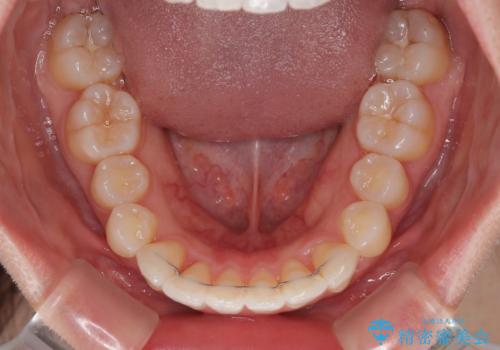

深い咬み合わせによる隙間 インビザライン矯正でコンプレックスを改善

- 上の前歯の隙間を気にして来院された患者様です。

インビザラインにより、上下の歯列を側方に拡大しつつ、前歯の隙間を閉じていくこととしました。

隙間の原因は強い咬合力や舌の突出癖、小帯の異常付着などがありますが、舌のトレーニングをしっかりと行いながら、装着時間を遵守して装着していただいたおかげで、スムーズに治療を終えることができました。